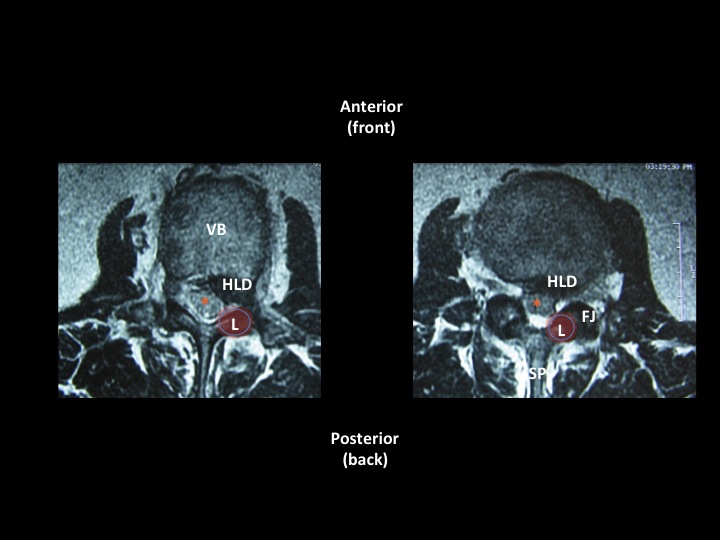

Images 2a & 2b (above left and right) show normal lumbar spinal structure/anatomy on an MRI (T2 seq.)